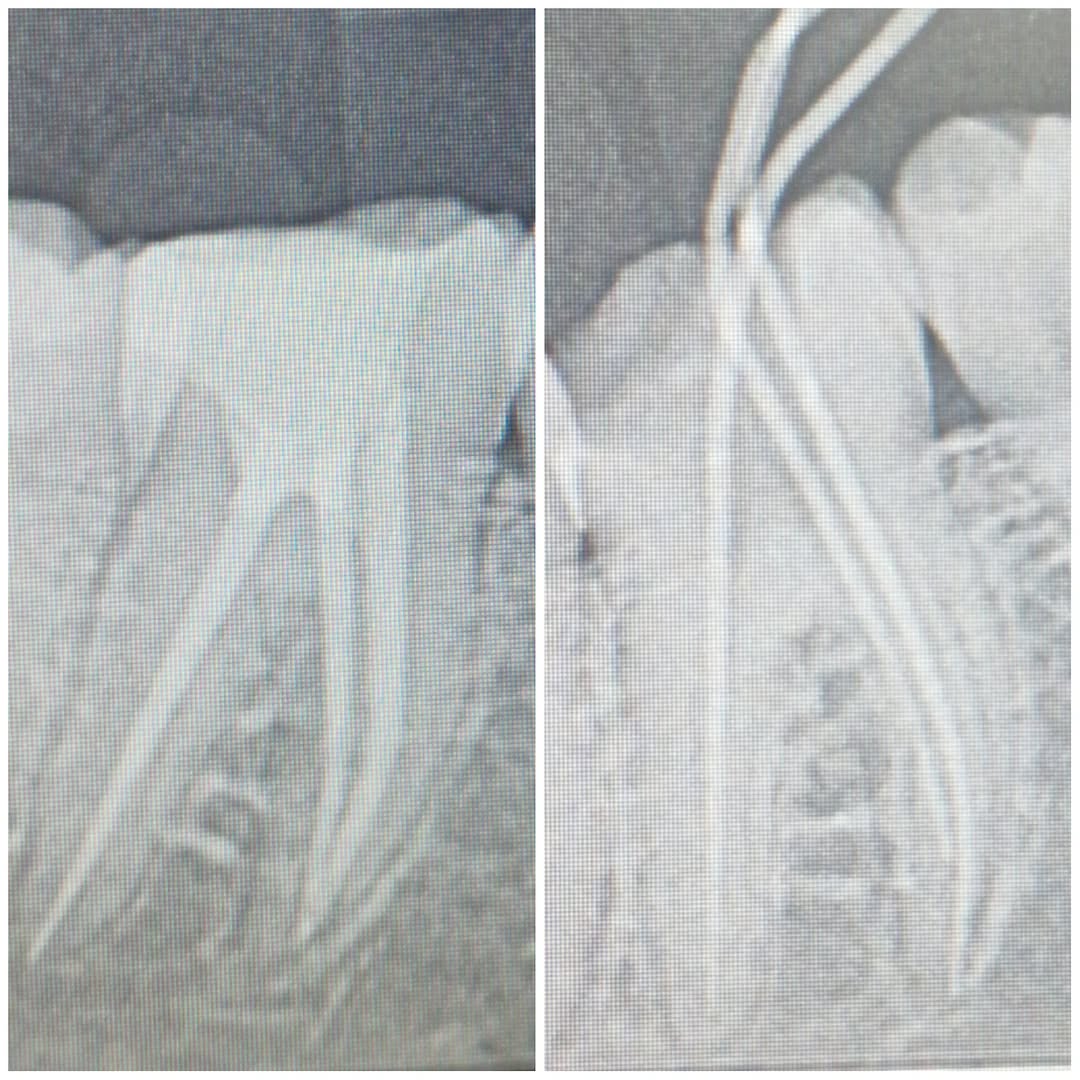

Single visit RCT. Patient with acute pulpitis, PPT+, acces gained, canals shaped with ProTaper Wave One Gold, GIC filling.

17